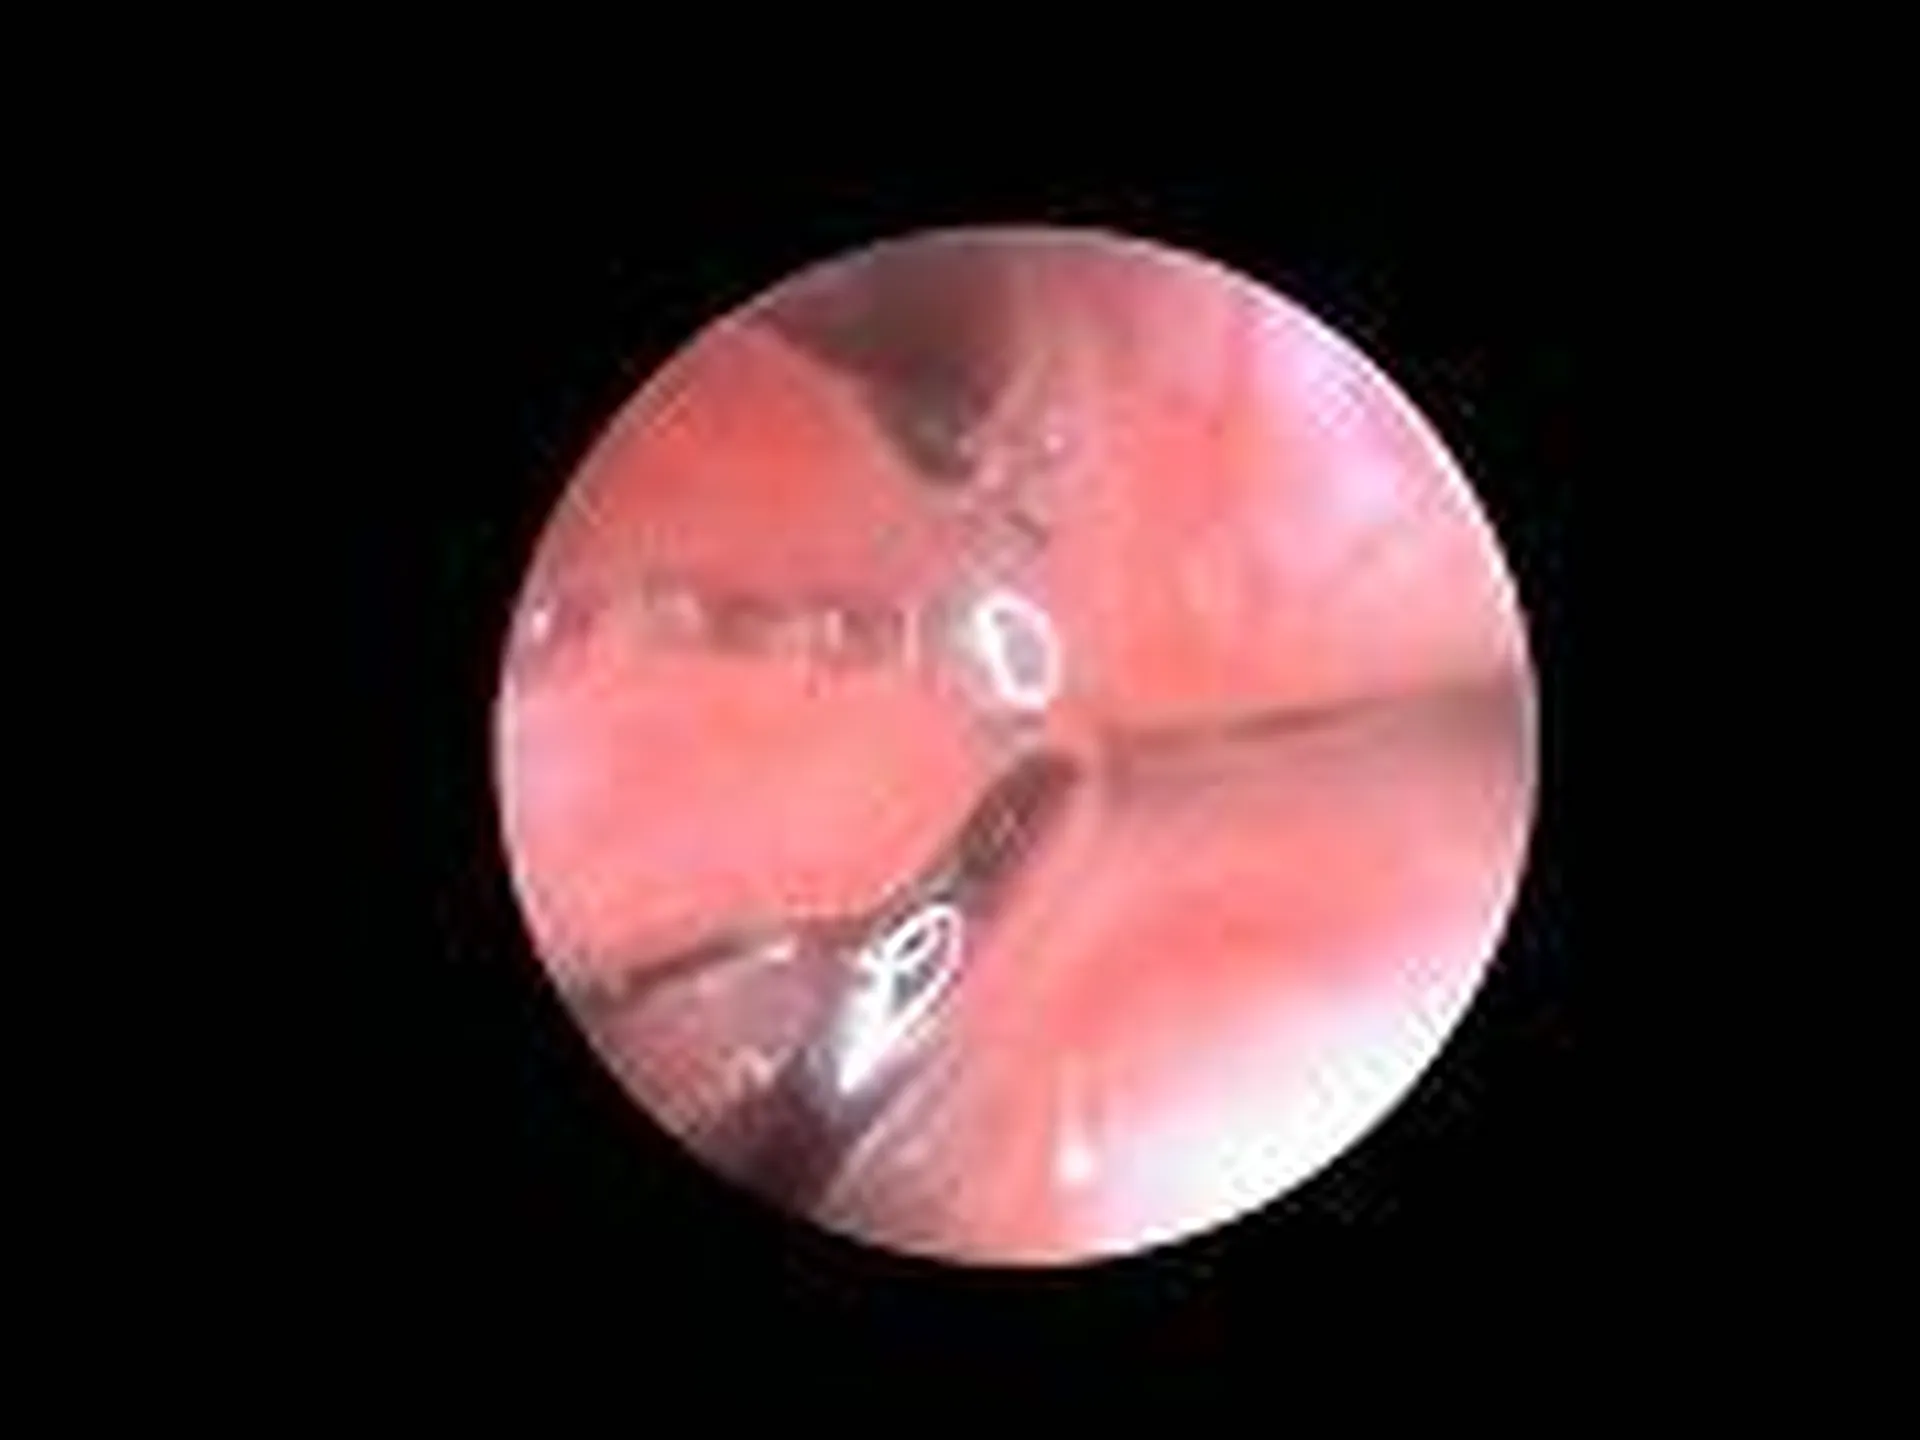

Une endoscopie consiste à l’utilisation d’une caméra afin de visualiser des structures, affections non accessibles facilement.

De nombreuses indications existent en endoscopie  que ce soit pour intervenir (retrait de corps étrangers), effectuer une biopsie (en cas de masse, tumeur),  visualiser (dilatation, lésion inflammatoire, ulcérée)

Affection touchant les narines (on parle de rhinoscopie) : retrait de corps étrangers, visualisation de processus cancéreux, infections nasales bactérienne ou fongique

Des clichés sont effectués tout au long de l’intervention afin que vous puissiez visualiser les affections notées au cours de l’examen.